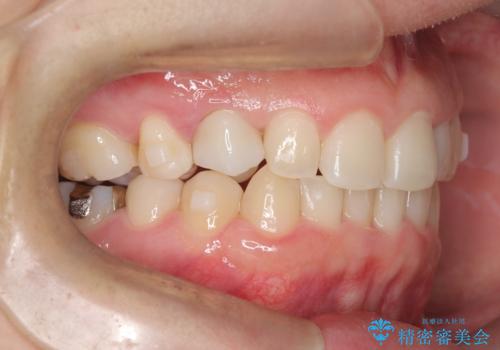

- 下の歯のがたつき(叢生)、真ん中(正中)が右にずれていることを主訴に来院されました。右上前から3番目の永久歯が埋まっている(埋伏)していることから正中は可能な限り合わせることをゴールとしてマウスピースでの矯正治療を選択しました。

今回の矯正治療では、透明なマウスピース型の装置インビザラインを使用しました。がたつきをとるため、安全性が確保できる範囲で歯と歯の間を少し削り必要なスペースを確保しました。